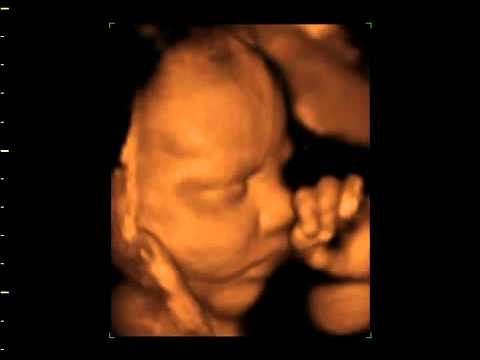

Gracias por tanto, por todo!👇🏽PWelcome to H&M, your shopping destination for fashion online We offer fashion and quality at the best price in a more sustainable way Las ecografías 3D y 4D son una técnica que permite ver una imagen tridimensional y en movimiento del bebé que aún está en el vientre de su madre, permitiendo de este modo un mejor seguimiento y representación de la actividad fetal Es el método más reciente que da la posibilidad a los padres no sólo de saber con más exactitud si su bebé es un niño o una niña, como de ver la

UNA PRIMERA ECO 4D Se realiza entre las semanas 12 a la , en la cual te desvelaremos la incógnita sobre el sexo del bebé Te entregamos un DVD con la grabación de la ecografía, de una media hora de duración Todas las fotos de la sesión en un CD Dos fotos del bebé en papel fotográfico y de alta calidadA partir de la semana 16 podemos determinar el sexo de tu bebé con una ecografía tradicional en 2D y se puede combinar con ecografía 3D y 4D a partir de la semana Sesión 3D 4D Si quieres tener un momento único y especial con tu bebé, una sesión de ecografía 3DEste es el momento ideal para realizar la ecografía estructural que permitirá valorar toda la anatomía de tu bebé El feto pesa entre 400 – 600 grs y mide entre 23 – 30 cm desde la cabeza al talón La madre ya percibe los movimientos fetales En esta ecografía, además de tomar las medidas de tu bebé, se realiza un examen detallado

ECO BEBE January 18 Pack de 5 pañales bamboo carbon referencia niña Este pack incluye 5 pañales de tela interior algodón y 5 insertos de 5 capas bamboo carbon Precio 0000 cop #pañalesdetela #pañaldetelacolombia #pañalesecologicos #pañalesecologicoscolombia #bebemedellin #bebescolombia #productosbebescolombia #Las ecografías 3D y 4D pueden realizarse en cualquier momento del embarazo aunque las mejores imágenes se obtienen entre las semanas 24 y 30 pues las condiciones son las más adecuadas La ECO 3D y 4D es peligroso para el bebé bueno mamis yo lei por aca en babycenter que esos ecos con el tiempo el bebé de nacido sufre algunos problemas de visión nose que tan cierto sean porq si fueran riesgosos el doctor no los aria oh también los doctores por,ganar dinero extra tambien asi que la verdad no se que tan cierto sean suerte mis pancitas BabyCenter